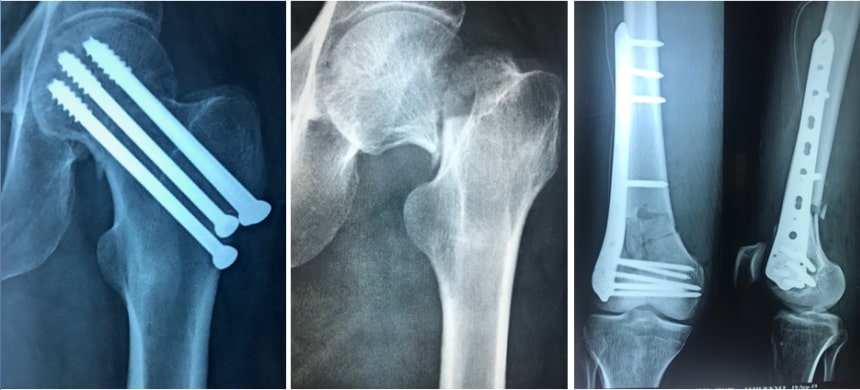

But if the fragments are displaced from each other then there is a lot of chance of non-union of the fracture. So this fracture should be fixed in the correct anatomical position. This kind of fixation needs the use of plates, screws etc. If we fix the fragments in good anatomical position and if the bone fragments get very good blood supply then the fracture will unite very well.

Most of the fractures of the leg bones are operated and fixed using this keyhole surgery. Most of the fractures of arm and forearm are fixed with plate and screws. Intra-articular fractures are the fractures involving the articular surface of bones. They need to be reconstructed properly. They should be fixed with proper implants. This fixation is very important to get back the moments of any joint.

Fixing fractures using metal plates and screws has been in practice for more than 50 years. Most of the times stainless steel has been used to make this kind of plate and screws. Nowadays titanium is being used as a preferred metal for the preparation of plates, screws, nails , locking nails and elastic nails. Both these implants are very good. But titanium has got some advantages over stainless steel. Titanium is not getting rusted and is more bio compatible. Titanium will not interfere with the CT scans. But it is costly comparing with stainless steel.